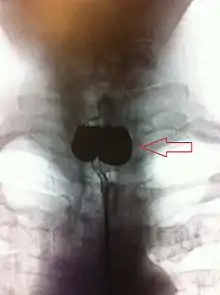

A Zenker's diverticulum, also pharyngeal pouch, is a diverticulum of the mucosa of the human pharynx, just above the cricopharyngeal muscle (i.e. above the upper sphincter of the esophagus). It is a pseudo diverticulum (not involving all layers of the esophageal wall).

A combination of the simple barium swallow and a thorough endoscopy will normally confirm the diverticulum.[4]